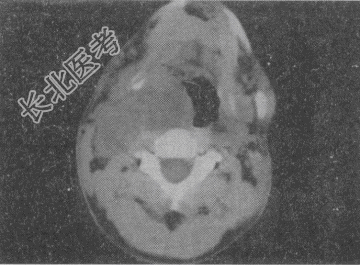

- 单项选择题男,41岁, 右侧咽部不适2年余,有异物感, 声音嘶哑,CT如图, 最可能的诊断是

A、颈动脉体瘤

B、咽旁转移瘤

C、咽旁淋巴瘤

D、小唾液腺瘤

E、咽旁神经鞘膜瘤